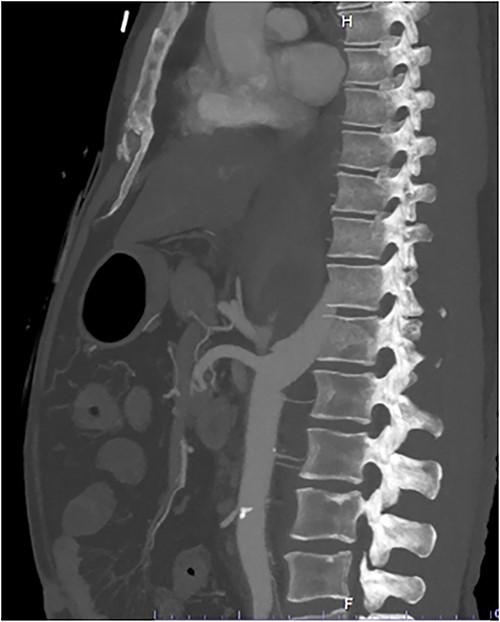

A 54-year-old male presented to our Level 1 Trauma Centre following a high-speed motor vehicle accident with rollover. Although initially haemodynamically stable, significant hypoxia prompted a trauma call activation. On arrival to the Trauma Centre, he had a Glasgow Coma Scale of 8 with an initial heart rate of 70 bpm and systolic blood pressure of 101 mmHg. A brief loss of cardiac output resulted in intubation, bilateral finger thoracostomies and the commencement of massive transfusion. Although his abdominal eFAST was positive, he was fluid responsive and proceeded to imaging. A full computed tomography (CT) trauma series demonstrated CA avulsion (Fig. 1) with contrast extravasation into the retroperitoneum and a large retroperitoneal haematoma measuring 18 cm by 9 cm (Figs 2 and 3). Nil visceral injury was identified and imaging otherwise revealed fractures of the left scapula, right 12th rib and bilateral acetabula and pubic rami.

Axial CT slice demonstrating coeliac trunk avulsion with active bleeding into a large retroperitoneal haematoma.

Coronal CT slice demonstrating coeliac trunk avulsion with active bleeding into a large retroperitoneal haematoma.